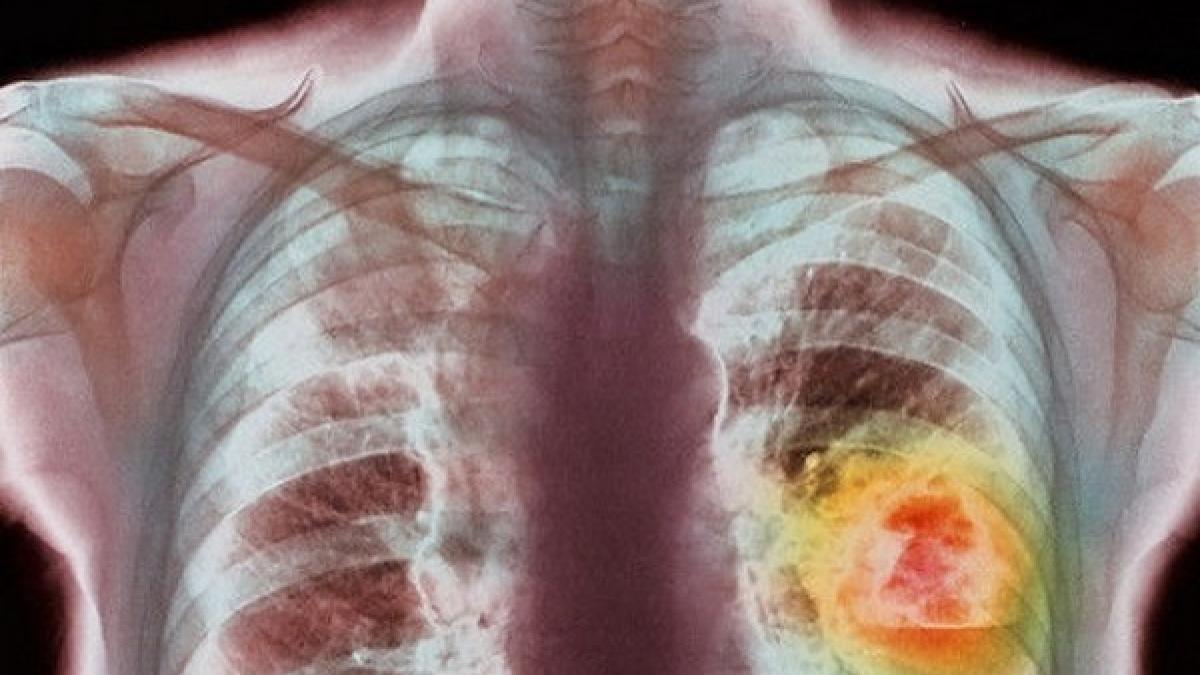

Cancer pulmonar. Două grupuri farmaceutice s-au aliat pentru a testa un medicament

Cancerul pulmonar a făcut 1,6 milioane de victime în 2012 (19,4 % din totalitatea formelor de cancer), înaintea cancerului de ficat (800.000, adică 9,1 %) şi a cancerului de stomac (700.000, adică 8,8 %), precizează descoperă.ro.

Cancerul pulmonar reprezintă o afecţiune care se caracterizează printr-o creştere celulară necontrolată a ţesuturilor plămânului. Dacă nu este tratată, această creştere se poate răspândi şi la nivelul ţesturilor din apropiere sau al altor organe din corp, prin intermediul metastazelor.

În 2012, potrivit Organizaţiei Mondiale a Sănătăţii (OMS), cancerul pulmonar se situa pe primul loc în privinţa numărului de cazuri diagnosticate (1,8 milioane de cazuri, adică 13 % din totalitatea formelor de cancer diagnosticate), înaintea cancerului la sân (1,7 milioane, adică 11,9 %) şi a cancerului de colon (1,4 milioane, adică 9,7 %).